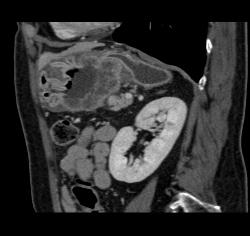

Antral Carcinoma With Adenopathy